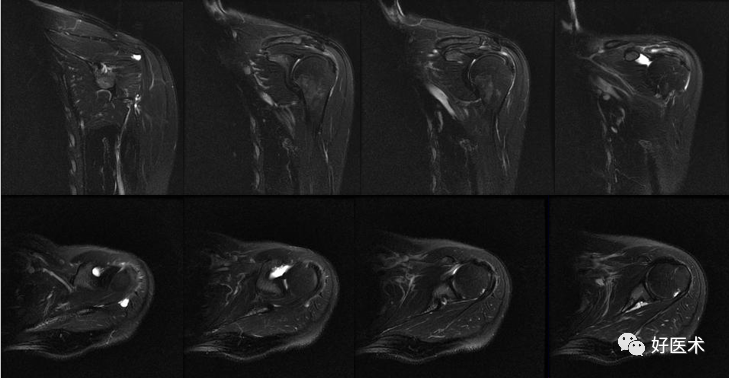

(2)肩袖撕裂

冈上肌腱最易发生。

部位:最易发生于距肱骨大结节1. 0cm 处所谓的危险区域 。

1)肌腱炎

肌腱形态可正常

T2WI肌腱内线状高信号,未累及上或下表面

肩峰-三角肌下脂肪层正常

2)部分撕裂

肌腱增厚、变薄、不规则;

肌腱的关节面或滑膜面撕裂,或肌腱内分离缺损,肌腱连续性存在;

斜冠面T1WI 上呈低至中等信号强度,PDWI呈中等到高信号,T2WI +FS上呈高信号强度;

T2WI+FS,肩峰下滑囊和三角肌下滑囊不应出现高信号(积液)。

3)完全性撕裂

原发征象:肌腱局部缺如,连续性液体信号横贯肌腱的全层,这使得盂肱关节和肩峰下滑囊相通。

继发征象:

①肩峰下滑膜囊积液,积液在T1WI /PDWI上呈中等信号,T2WI+FS上呈高信号;

②冈上肌肌肉、肌腱结合处回缩(正常位置在肱骨头上方);

③滑囊旁脂肪垫的渗出丢失。

MR 关节造影:局限性或弥漫性充满造影剂的裂隙贯穿肌腱全层,肌腱失去其连续性。

正常、异常肩袖肌腱和邻近软组织结构的MR表现

冈上肌肌腱撕裂可分为全层或部分,部分撕裂又分为下表面(关节面)撕裂、上表面(滑囊侧)撕裂及腱内撕裂。据文献报道,冈上肌肌腱下表面撕裂最常见,可为上表面撕裂的2~3倍,腱内撕裂则最少见。

冈上肌肌腱下表面撕裂发病率高可能与肩关节不稳并内撞击,肩关节侧肌腱纤维延展性较差有关。

诊断冈上肌肌腱部分撕裂的金标准是肩关节镜,但是腱内撕裂常易漏诊。

冈上肌腱不完全撕裂

冈上肌腱不完全撕裂伴肩峰下囊积液

冈上肌肌腱损伤(撞击),肩胛下滑囊积液(肩胛下肌腱损伤?)

冈上、下肌腱撕裂、肩胛下囊积液